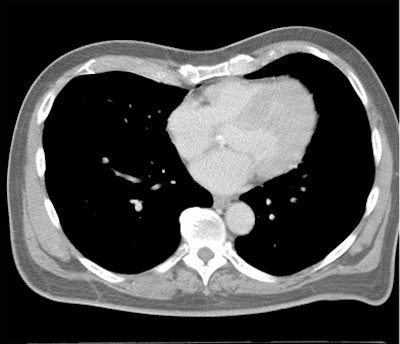

Which image would you rather be responsible for? Small 13-cm FOV (above) provides the best cardiac image quality at the lowest radiation dose compared with medium 25-cm FOV coronary CTA image (below). Thoracic image (bottom) maximizes anatomic coverage but at the cost of additional radiation and potentially more incidental findings. All images courtesy of Dr. Matthew Budoff.

From there, expanding the FOV to the entire thorax for screening of other important findings (lung, breast, axilla, mediastinum, and spine) would actually boost the radiation dose by 67.5%, he said.

Of course, more anatomic coverage is often needed, Budoff said. Sometimes the radiologist needs to look for aortic dissection or pulmonary embolism, but at that point it's not a heart study.

"What I call a cardiac CT always includes the great vessels, the myocardium, the left and right atrium, and pericardium," Budoff said. "I'm never only interested in the coronary anatomy. But in cardiac CT, I'm never interested in the lung. If I'm interested in the lungs, I can do a dedicated lung scan for an additional 0.7 mSv of radiation and have it interpreted separately and done properly."